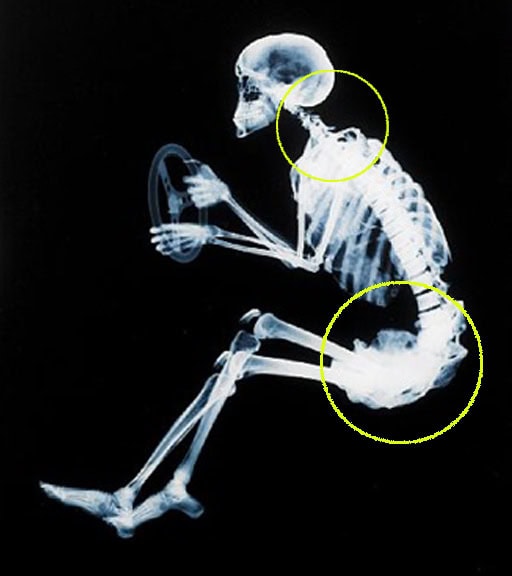

Frederick Matthias Alexander Con il termine movimentazione manuale dei carichi (MMC) si intendono le operazioni di trasporto o di sostegno di un carico ad opera di una o più persone. Queste azioni includono... Tensione muscolare al collo: cause La tensione muscolare al collo o alla schiena sono un male diffuso, tant'è che molti di noi si rassegnano a conviverci per tutta la vita.

La relazione tra la testa, il collo e la schiena è ciò che F.M. Alexander ha chiamato il Controllo Primario. La qualità di questo rapporto... Metodo Feldenkrais VS Tecnica Alexander Il metodo Feldenkrais e la Tecnica Alexander sono attività correlate. Il metodo Feldenkrais prende il nome dal suo ideatore, il Dr. Moshe Feldenkrais (1904-1984), come anche la Tecnica Alexander (F. M. Alexander, 1869-1955). La Tecnica Alexander è stata sviluppata qualche decennio prima del metodo Feldenkrais, inoltre quest’ultimo è in parte derivato dalla Tecnica Alexander (anche... Morbo di Parkinson: come muoversi meglio Tra i disordini del movimento il Morbo di Parkinson è in assoluto il più frequente. Si tratta di una malattia neurodegenerativa caratterizzata da un'evoluzione piuttosto lenta, ma progressiva che coinvolge le strutture cerebrali profonde che permettono la corretta esecuzione dei movimenti.

La Tecnica Alexander ci... Spalle Alte Uno dei principali elementi che disturbano la nostra postura e il nostro portamento sono le cosiddette spalle alte, un problema non solo estetico ma anche - e soprattutto - funzionale.

Molte persone infatti soffrono di dolori e contratture croniche al collo, alle spalle e alle braccia (polsi e mani inclusi) perché durante le ore di veglia... La colonna vertebrale: sai come dovrebbe funzionare? La colonna vertebrale, tutti l'abbiamo ma in pochi si chiedono come dovrebbe funzionare.